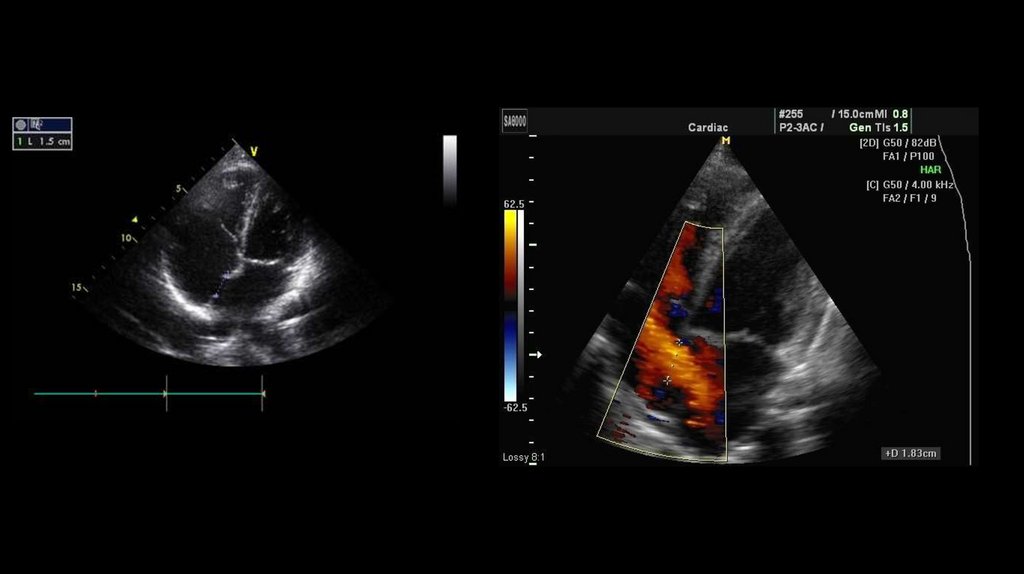

13. ЭхоКГ открытого артериального протока

• Эхокардиография (ЭхоКГ) дает исчерпывающие данные о состоянии сердца. Она

позволяет визуализировать дефект и вторичное изменение геометрии сердца,

визуализировать сброс с помощью цветной допплерографии, подсчитать

отношение легочного кровотока к системному, оценить систолическое давление в

правом желудочке, диагностировать сопутствующие пороки сердца.